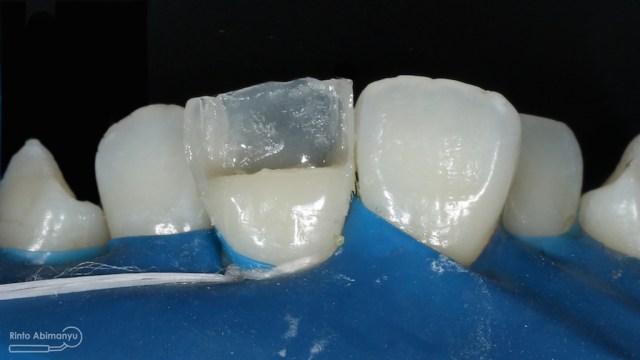

Sementasi menggunakan semen resin Relyx Ultimate (3M) dan bonding Scotchbond Universal (3M) dilakukan isolasi maksimal daerah sekeliling gigi pada sementasi tersebut…

Begini hasil akhir setelah sementasi crown…

Foto klinis setelah pemasangan crown